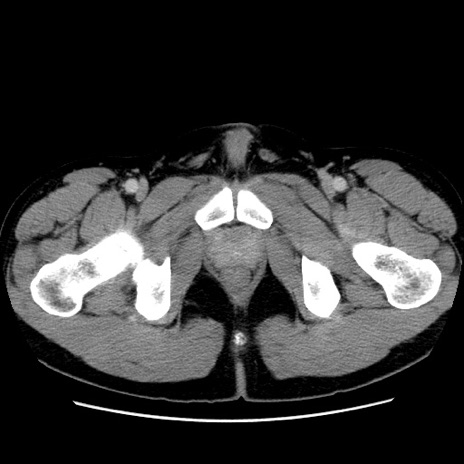

症例4(横断像)

【症例】30歳代男性

【主訴】腹痛、嘔吐

【現病歴】昨晩から突然の腹痛あり、その後嘔吐、軟便も出現。腹痛が改善しないため救急搬送となる。2日前にしめ鯖の食事歴あり。

【身体所見】意識清明、苦悶様、BP 135/90mmHg、BT 35.7℃、腹部:平坦、やや硬、心窩部〜臍部に自発痛、圧痛あり、筋性防御+、反跳痛-

【データ】WBC 8100、CRP 0.57